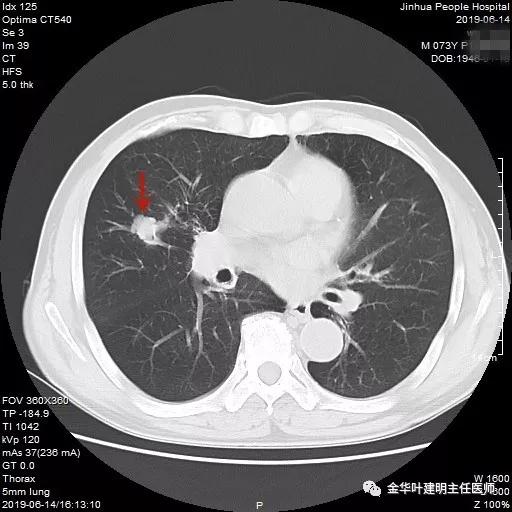

吴某不同意肺穿刺,咳嗽咳痰好转后就出院了。此后于今年6月份回院复查,仍然住在内科,这次想通了,同意肺穿刺,结果病理果然是肺癌,是低分化鳞癌。因为吴某与本院一院级领导是同村的,便让我去会诊。我觉得虽然从病灶来看可以手术,纵隔内也无明显转移的肿大淋巴结,相关检查也无远处转移证据。但患者年纪较大,平时有慢支与肺气肿,发作时还有喘憋症状,肺功能也示重度混合型通气功能障碍,MVV重度下降。询问吴某,平时一口气走上3楼是有困难的,所以行右肺上叶切除术后出现呼吸功能不全的概率还是比较高的,手术存在较大风险。争取手术也是为争取根治以至得到较长期生存的机会。若同意手术,也要家属与患者都十分理解,并对术后需要呼吸机辅助以及无法脱离呼吸机支持都有充分的思想准备。而若放弃手术,则主要是免疫治疗及放化疗,其中放化疗对肺功能也有一定影响,且无法达到根治的目的。我当时告诉吴某儿子,要开,做好术后出现呼吸功能衰竭的准备,且不能责怪我的同事和我本人;若暂不手术,也可回当地考虑保守治疗;当然也可先戒烟、锻炼肺功能、使用支气管扩张剂等改善肺功能,较短时间内再回院复查肺功能,再争取手术。吴某当时办理了出院手续,也没有与我们确认是否考虑手术。下面是当时6月份时候的片子以及肺穿刺情况:

绿色箭头示穿刺针,红色箭头示肿瘤